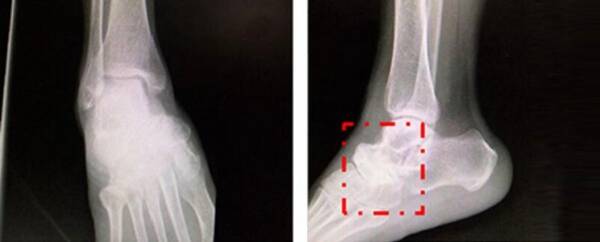

經(jīng)懷集縣人民醫(yī)院進(jìn)行X線片、CT、MR等傳統(tǒng)影像檢查,初步診斷為:1.右足舟骨壞死。2.右距舟關(guān)節(jié)骨關(guān)節(jié)炎。3.右跟骰關(guān)節(jié)骨關(guān)節(jié)炎。擬行右距舟關(guān)節(jié)、跟骰關(guān)節(jié)融合術(shù)。

圖片來源:丁煥文教授團(tuán)隊(duì)